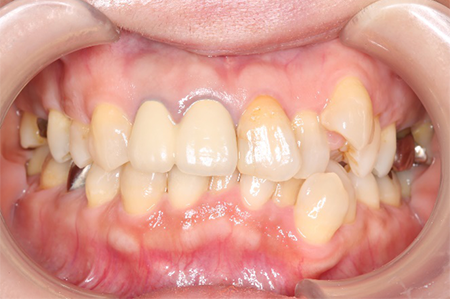

前から見ても歯が欠けてしまい、歯茎も赤く腫れてしまっているのが分かります。

矯正治療と言っても、成人で虫歯の治療などが多数歯に渡って既に施されている場合、被せ物を変えていく必要があるのか、虫歯はないか、抜歯をする必要があるか、考えないといけないことがたくさんあります。

下の口腔内写真は初診時と矯正治療+補綴治療後のものになります。

連結してあった前歯の被せ物(歯茎まで黒くなっている)も矯正後にきれいに治療することが出来ています。

歯並びが悪いと見た目が悪いだけではなく歯磨きがしづらく、噛み合わせが悪いことで力のかかり方が不均一になってしまい歯に亀裂が入り虫歯になりやすくもなります。